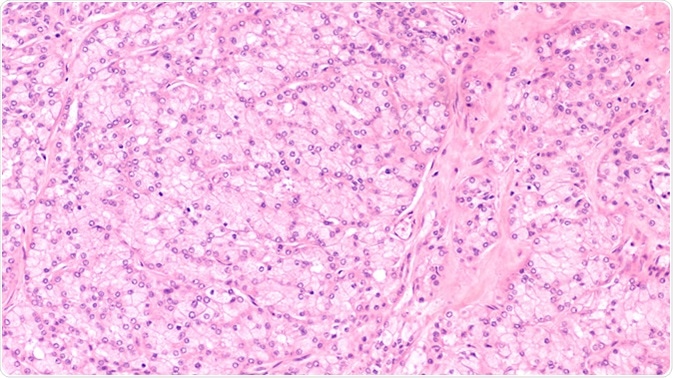

Microscopic image of an acinic cell carcinoma, a rare cancer of salivary glands such as parotid, submandubular or sublingual gland. They derive from acinar cells and have finely granular cytoplasm. - Image Credit: By David Litman / Shutterstock

Acinic cell carcinoma is a rare cancer of the salivary glands that originates from the parotid gland. It is a low-grade salivary neoplasm that constitutes about 5% to 17% of cases involving salivary gland malignancies. In comparison with other salivary gland cancers, acinic cell carcinoma is relatively slow-growing, and progresses among younger individuals. The prognosis of this type of cancer heavily depends on the rate of its metastasis. Acinic cell carcinoma is more prevalent in women than in men.